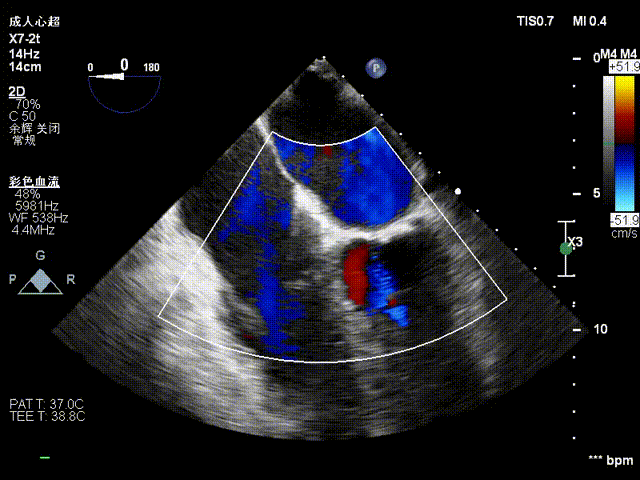

术前影像

二尖瓣后瓣腱索断裂并脱垂及关闭不全(重度)